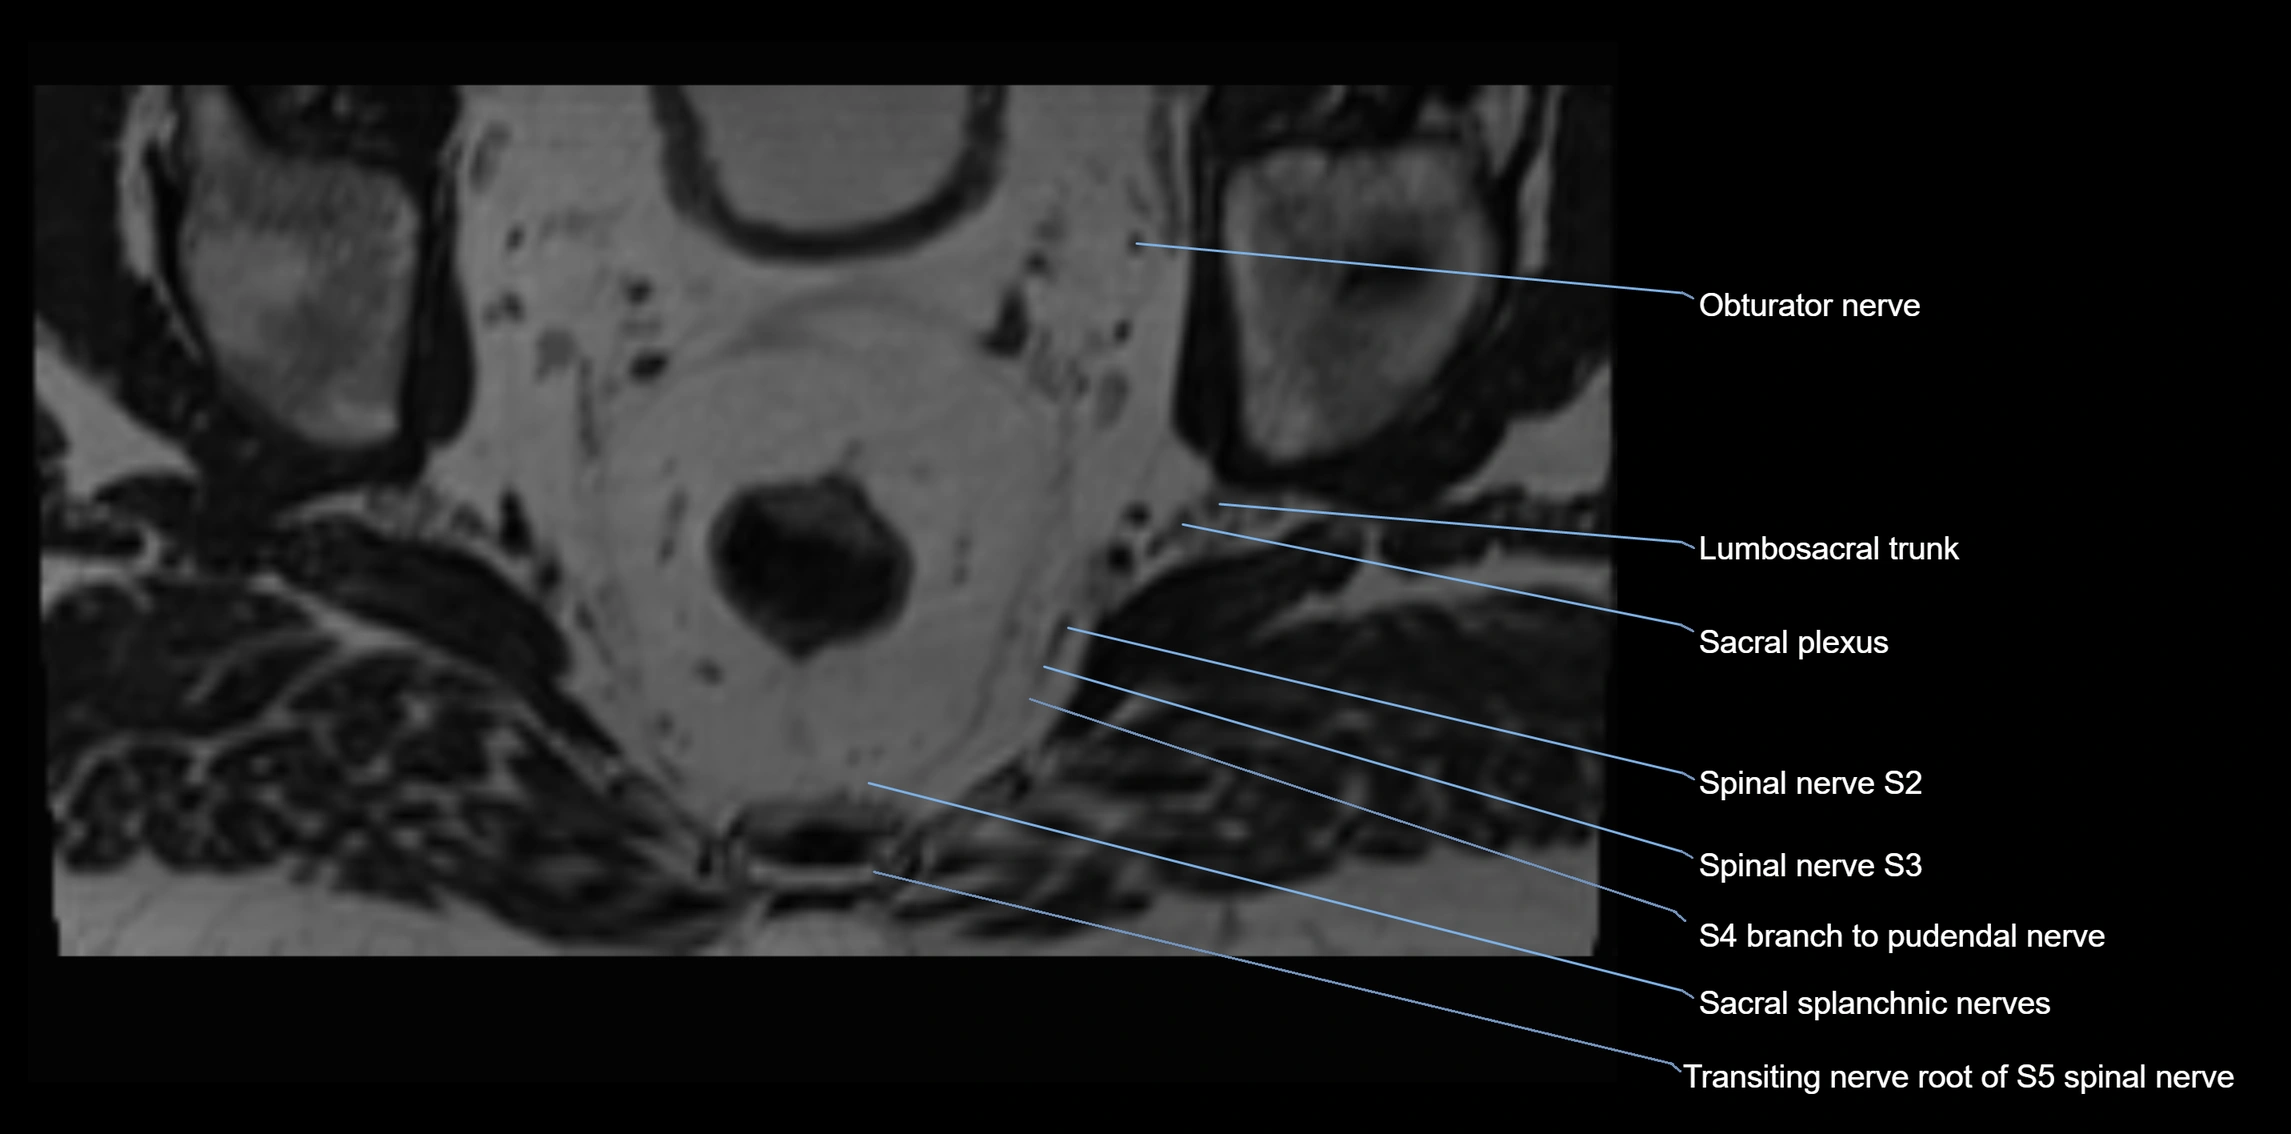

MRI image

image